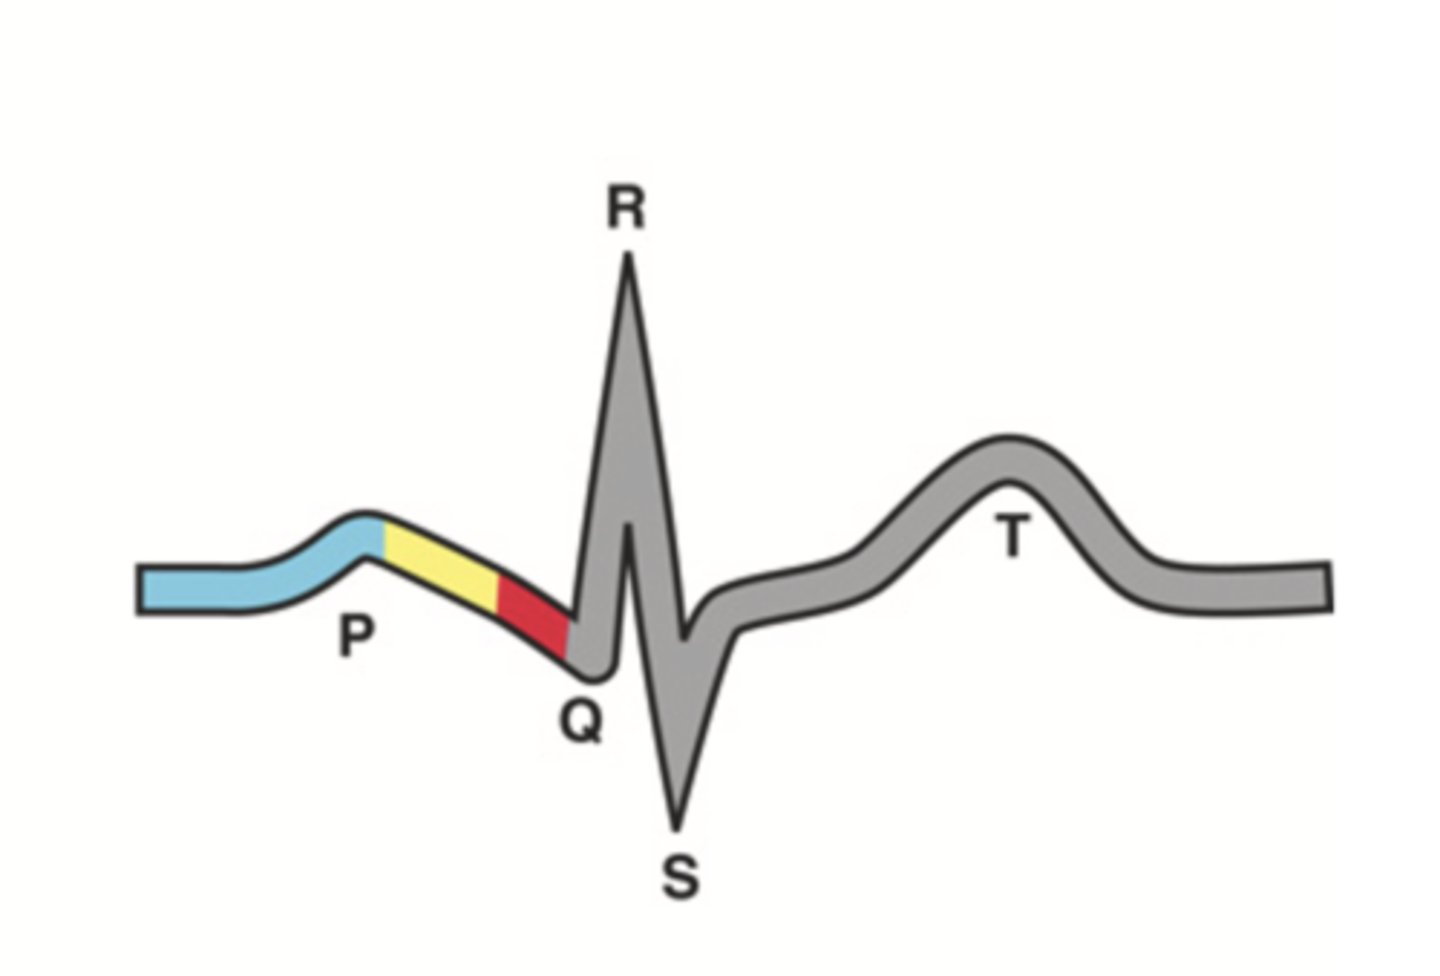

4 Parts of the Heart's Conduction System

- Sinoatrial (SA) node

- Atrioventricular (AV) node

- Bundle of His

- Purkinje fibers

Sinoatrial (SA) Node

Pacemaker of the heart conduction system, located at the right atrium (light blue)

Atrioventricular (AV) Node

The part that relays electrical impulses from atria into the bundle of his in the heart's conduction system; delayed slightly (yellow)

Bundle of His

Part of the heart's conduction system that transmits the cardiac impulse from the atrioventricular node to the purkinje fibers (red)

Purkinje Fibers

Fibers in the ventricles that transmit impulses to the right and left ventricles, causing them to contract

ECG Waves

- P wave

- P-R interval

- QRS complex

- Q-T interval

- T wave

P Wave

Atrial depolarization

P-R Interval

Atrial contraction

QRS Complex

Ventricular depolarization

Q-T Interval

Ventricular contraction

T Wave

Repolarization of ventricles